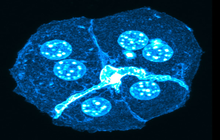

- Immunocytochemistry (ICC) technique

- Immunohistochemistry (IHC) technique

- Examination of cell placement on tissue scaffolds with SEM microscopy

On the other hand, in cutting-edge sciences such as tissue engineering, the use of up-to-date techniques for section preparation and cell tracking and engineered tissue structure has contributed significantly to the development of new studies.